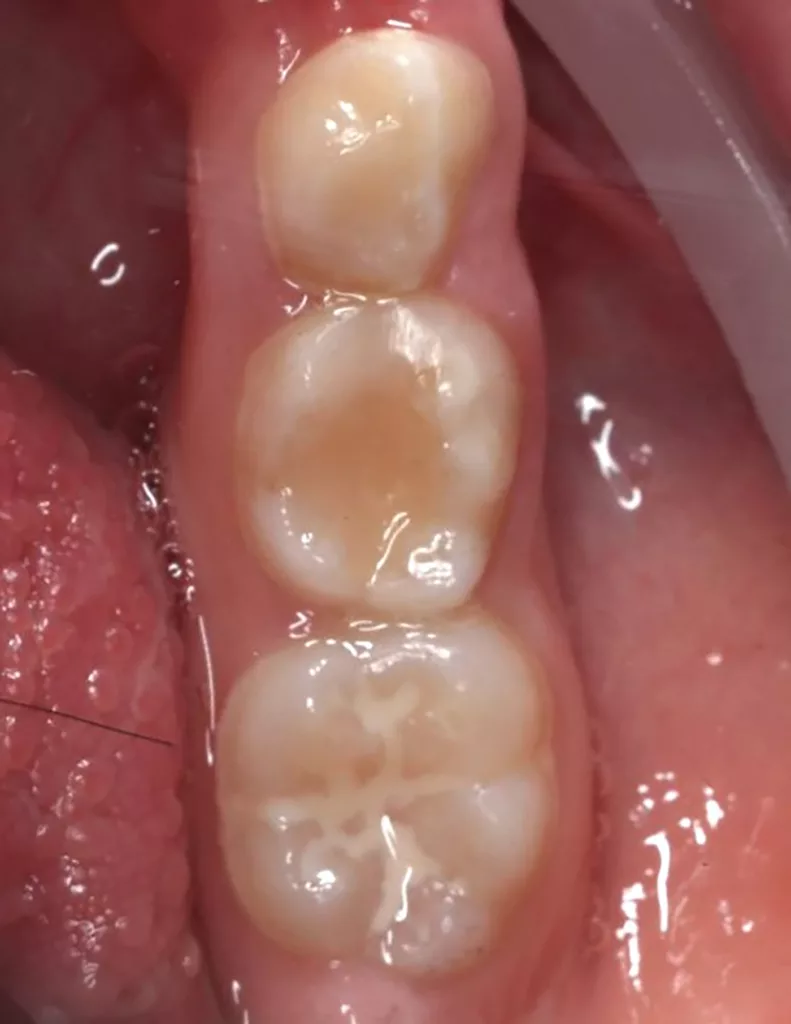

Im Rahmen der jährlichen Kontrolluntersuchung wurde bei einem achtjährigen Mädchen auf der routinemäßig angefertigten Röntgenaufnahme eine mittelgroße PEIR des Zahnes 46 (Grad 2 der Läsion nach Seow) entdeckt (Abb. 43). Die Patientin war komplett beschwerdefrei und der Zahnschmelz des betroffenen Zahnes sah intakt aus (Abb. 44 und 45). Weil auch hier der PEIR-Defekt gräulich durchschimmerte (Abb. 44 und 45) und der Zahn bereits seit einem Jahr durchgebrochen war, entschieden wir uns in diesem Fall, den Defekt klassisch mit Komposit zu restaurieren. Unter Lokalanästhesie mit Septanest 1/100 000 (Septodont, Frankreich) wurde zunächst Kofferdam mithilfe der Klammer U67 (KSK Dentech, Japan) gelegt (Abb. 45). Weder visuell noch mittels Sondierung konnte eine Verbindung zur Läsion festgestellt werden. Deswegen wurde an der Stelle, an welcher der PEIR-Defekt gräulich schimmerte, intakter Zahnschmelz der lingualen Querfissur entfernt (Abb. 46). Innerhalb der Läsion wurde nekrotisches intrakoronales Weichgewebe vorgefunden (Abb. 47), das problemlos mittels RONDOflex plus 360 (KaVo Dental, Deutschland) mit dem 27-µm-Pulver vollständig entfernt werden konnte. Der Boden des Defektes zeigte eine glatte, runde Form sowie helles, hartes und intaktes Dentin. Eine Präparation war nicht erforderlich, es wurde lediglich die Zahnschmelzkante geglättet (Abb. 48). Für die Restauration kamen erneut das Adhäsiv Optibond FL (Kerr, USA) und das Komposit Estelite ASTERIA OCE, A2B und Universal Flow AO2 (Tokuyama, Japan) zur Anwendung (Abb. 49). 6 Monate nach der Behandlung zeigte sich das Ergebnis sowohl aus klinischer als auch radiologischer Sicht stabil wie die Abbildungen 50 und 51 zeigen.

Fall 5